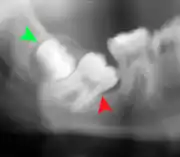

Panoramic radiograph of impacted lower wisdom teeth (green arrows) in a 26-year-old with dental caries (red arrows) on the adjacent teeth

The diagnosis of impaction can be made clinically if enough of the wisdom tooth is visible to determine its angulation, depth, and if the patient is old enough that further eruption or uprighting is unlikely. Wisdom teeth continue to move to the age of 25 years old due to eruption, and then continue some later movement owing to periodontal disease.[18]

If the tooth cannot be assessed with clinical exam alone, the diagnosis is made using either a panoramic radiograph or cone-beam CT. Where unerupted wisdom teeth still have eruption potential several predictors are used to determine the chance of the teeth becoming impacted. The ratio of space between the tooth crown length and the amount of space available, the angle of the teeth compared to the other teeth are the two most commonly used predictors, with the space ratio being the most accurate. Despite the capacity for movement into early adulthood, the likelihood that the tooth will become impacted can be predicted when the ratio of space available to the length of the crown of the tooth is under 1.[5]:141

Impacted 2nd molar (red arrow) with developing wisdom tooth (green arrow)

There is no standard to screen for wisdom teeth. It has been suggested, absent evidence to support routinely retaining or removing wisdom teeth, that evaluation with panoramic radiograph, starting between the ages of 16 and 25 be completed every 3 years. Once there is the possibility of the teeth developing disease, then a discussion about the operative risks versus long-term risk of retention with an oral and maxillofacial surgeon or other clinician trained to evaluate wisdom teeth is recommended. These recommendations are based on expert opinion level evidence.[19] Screening at a younger age may be required if the second molars (the "12-year molars") fail to erupt as ectopic positioning of the wisdom teeth can prevent their eruption. Radiographs can be avoided if the majority of the tooth is visible in the mouth.